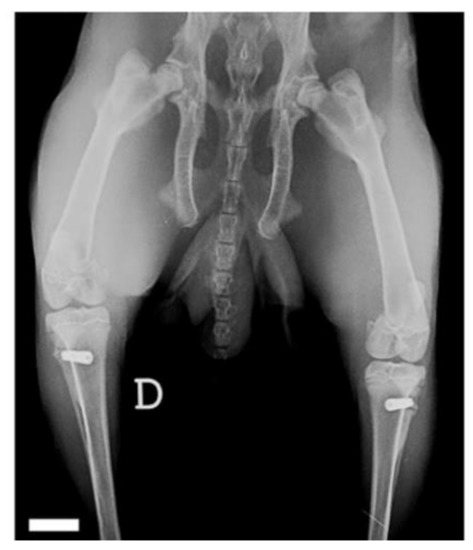

2.1. Surgical Procedure

2.2. Experimental Procedure